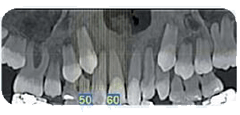

ContattiLa tua salute è al centro dell’impegno quotidiano dello Studio Braconi a Terni che, per garantirti servizi diagnostici tempestivi e precisi, si avvale esclusivamente delle migliori strumentazioni presenti sul mercato, come il nuovissimo Orthophos SL 2D: si tratta di un apparecchio specifico per l’analisi ortodontica, composto da due innovazioni, il Sharp Layer e il sensore DCS. Qui, con tempi di attesa ridotti, potrai usufruire di una qualità dell’immagine senza precedenti, dove la nitidezza è garantita anche nella valutazione dei casi più complessi e l’emissione delle radiazioni è sempre bassissima.

L’obiettivo dell’analisi è quello di valutare lo stato della bocca prima di eseguire un qualsiasi trattamento odontoiatrico, andando a evidenziare eventuali lesioni ossee, infiammatorie o cistiche; analizzare lo stato di salute della dentizione, soprattutto nelle fasi di sviluppo; tenere sotto controllo eventuali malformazioni o constatare la presenza di neoplasie mascellari o mandibolari.